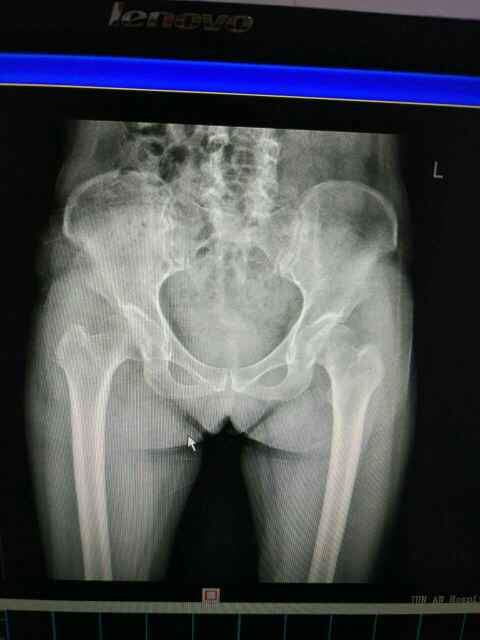

左股骨颈(头下型)骨折,断端稍先嵌插 已有1人参与

患者女,体重43kg ,年龄52岁。骑自行车摔跤了,医生结论,左股骨颈(头下型)骨折,断端稍先嵌插。请问这样的情况严重吗?保守医疗和手术哪个好些?手术的话风险大不大? 发自小木虫Android客户端 |